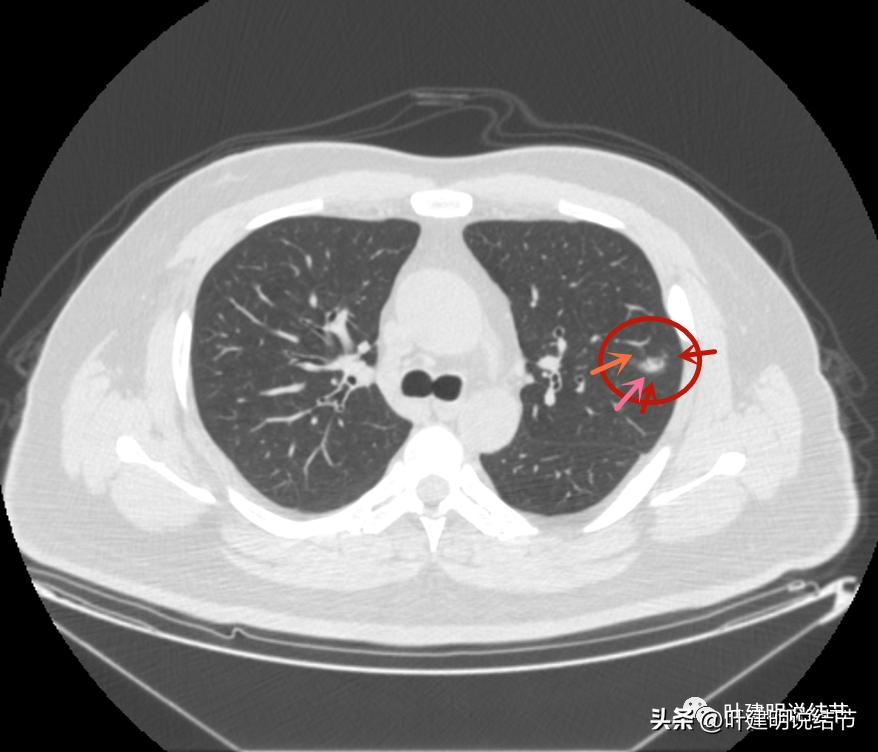

左上病灶1:磨玻璃结节,轮廓清楚伴微血管进入,中间似乎有空泡征,感觉像原位癌或不典型增生;

左上病灶2:混合磨玻璃结节,密度偏高,边缘稍糊,但轮廓相对清,有微血管分支进入,考虑微浸润性腺癌或浸润性腺癌可能大;

左上病灶3:混合磨玻璃结节偏实性,内部密度不均,整体轮廓清,有浅分叶,也有小血管关系密切,考虑浸润性腺癌可能性大;

左上病灶4:舌段磨玻璃结节,边缘显力糊,整体轮廓较清,不典型增生可能性大点。